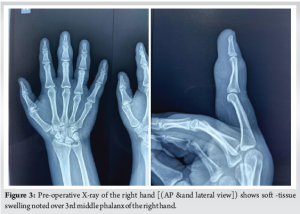

Plain radiographs of the right hand showed soft-tissue swelling (Fig. 3). Given the clinical suspicion, an MRI was performed (Fig. 4), revealing a small lobulated T1 and T2 hypointense subcutaneous soft-tissue lesion in the middle finger at the proximal and middle phalangeal level, extending between the flexor tendon and middle phalanx, measuring approximately 16 × 14 × 10 mm (CC × TR × AP), with surrounding soft-tissue edema. No evidence of bony infiltration was noted. The features were suggestive of a benign soft-tissue lesion (?TGCT). A small focal vascular ectasia was also noted in the index finger, measuring approximately 9 × 5 mm.